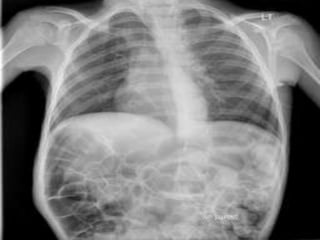

RESPIRATORY

Chest muscles and bones protect lungs. Muscles are essential for breathing. Respiratory system

provides oxygen and removes carbon dioxide.